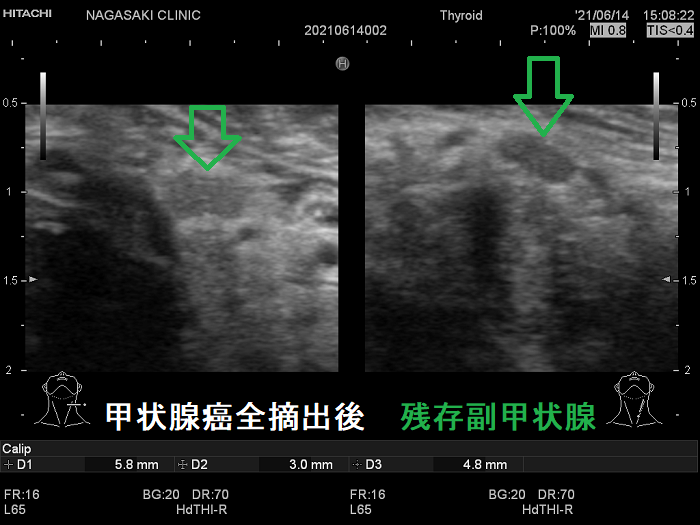

- 甲状腺摘術後、TSH 抑制療法;バセドウ病/甲状腺腫瘍で甲状腺切除と同時に副甲状腺も取ってしまった場合、取らずに温存した場合でも副甲状腺への血管を傷つけた場合

- 甲状腺全摘術時、副甲状腺も1-4腺を同時切除、あるいは切除しなくても栄養血管を損傷

- 術後副甲状腺機能低下症による低カルシウム血症;術直後のみならず、10年~30年以上して著明な低カルシウム血症で発症する事もある(日腎会誌 2012;54(1):40-47.)(J Clin Diagn Res. 2017 Feb; 11(2): OD07–OD09.)。

ケース①

ケース②